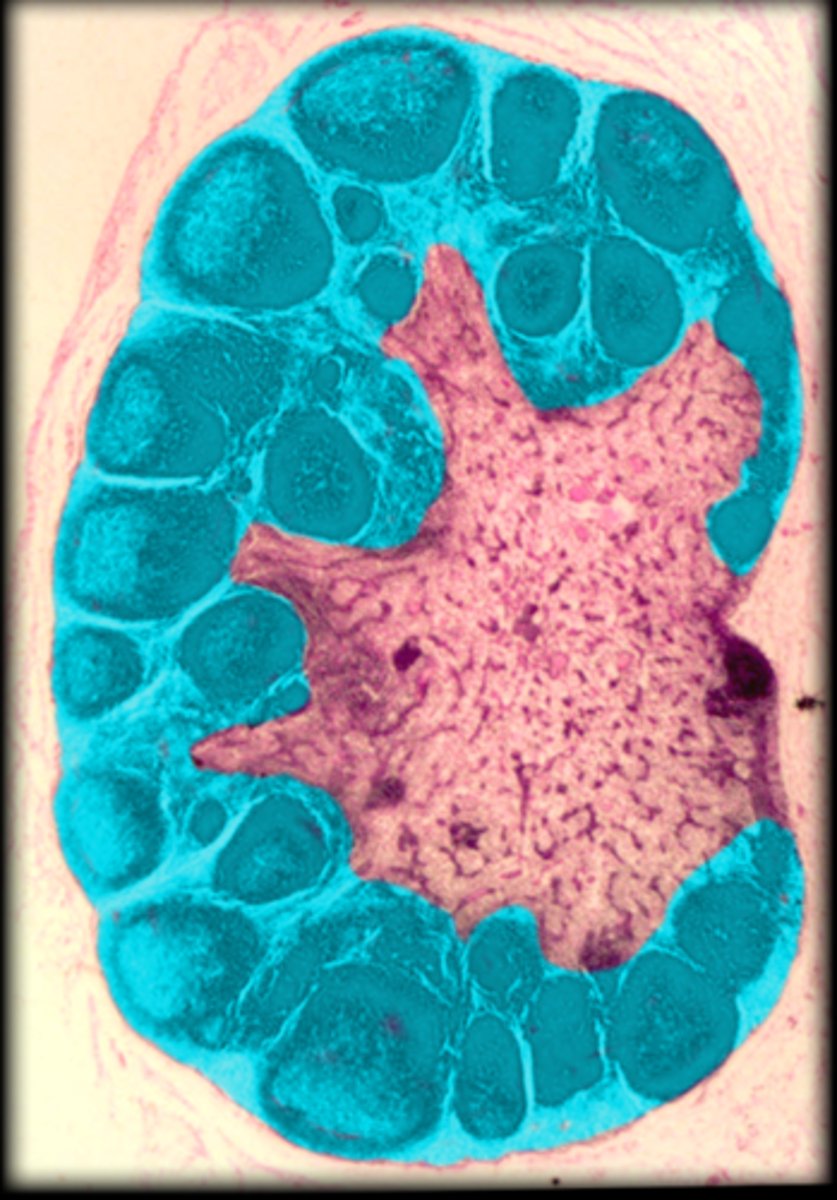

capsule

Lymph node

cortex

medullary cord

medullary sinus